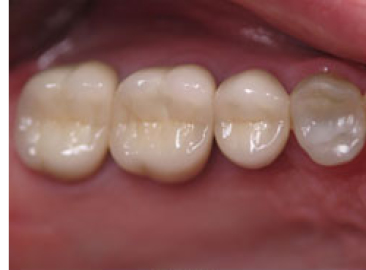

These are full crowns. Before shows old failing amalgam restorations.